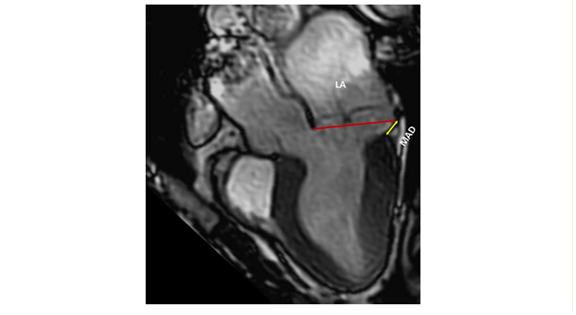

As for echocardiography, it is imperative to document key mitral valve characteristics, including bileaflet MVP and myxomatous MVP. The assessment should encompass measurements of the mitral annulus at both end-systole and end-diastole in both anteroposterior and inter-commissural aspects. Additionally, factors such as leaflet diastolic thickness, leaflet length, prolapsed distance, and the presence or absence of systolic curling, if applicable, should be mentioned, and quantification is necessary (8).

A comprehensive evaluation of MAD around the mitral annulus involves acquiring six left ventricular long-axis cine sequences with a 30° interslice rotation. Assessing MAD severity typically requires measuring its longitudinal length, at least from the long-axis view, and possibly its circumferential extent expressed in degrees (8,9,10).